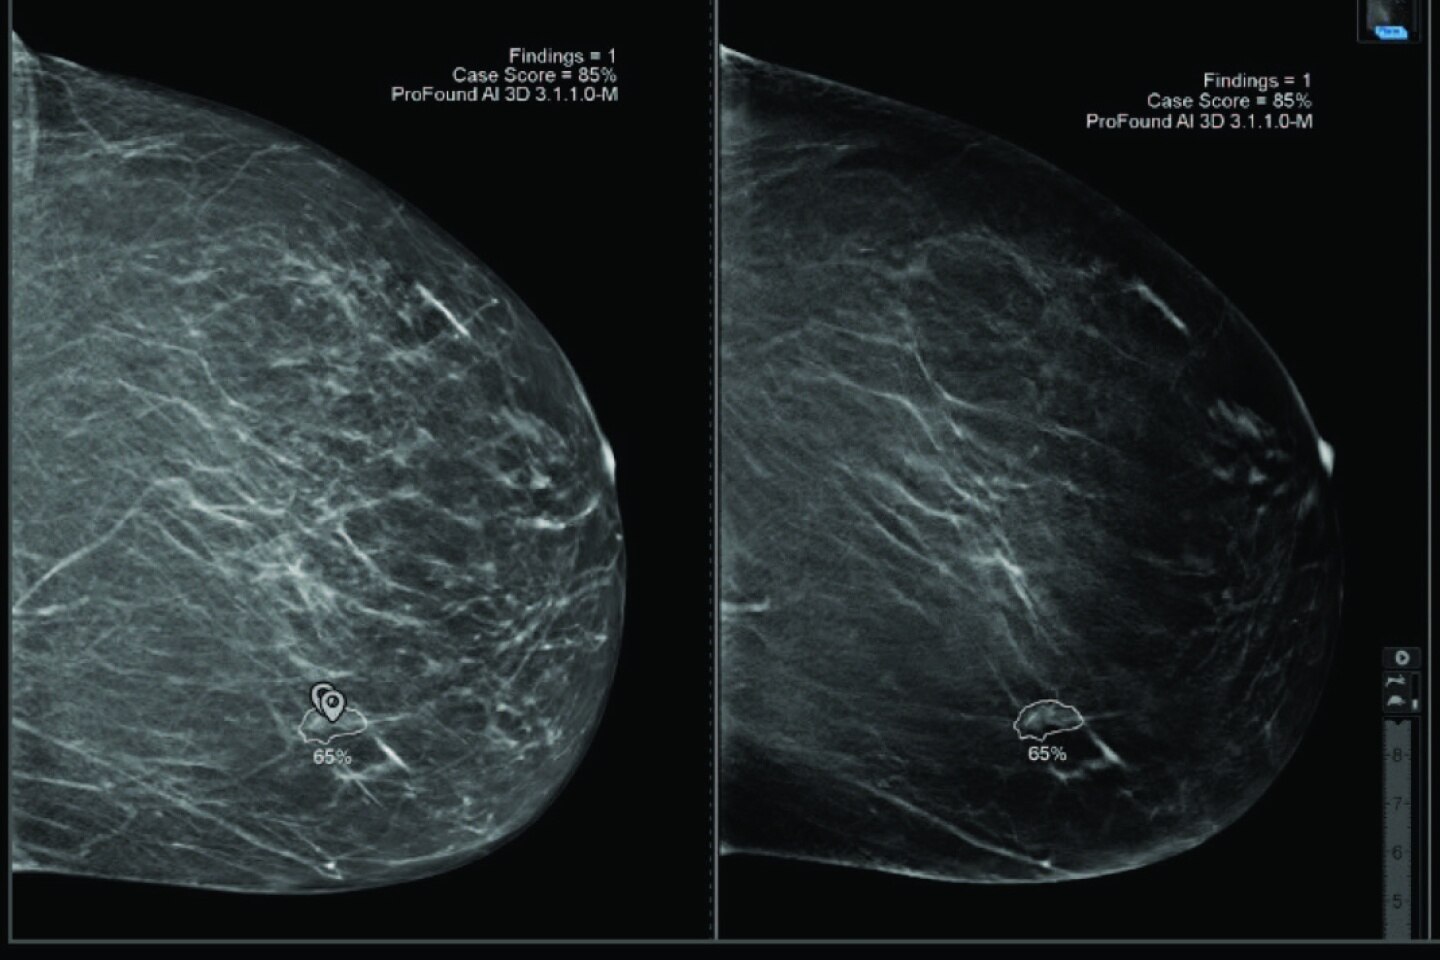

ProFound AI® pour la tomosynthèse